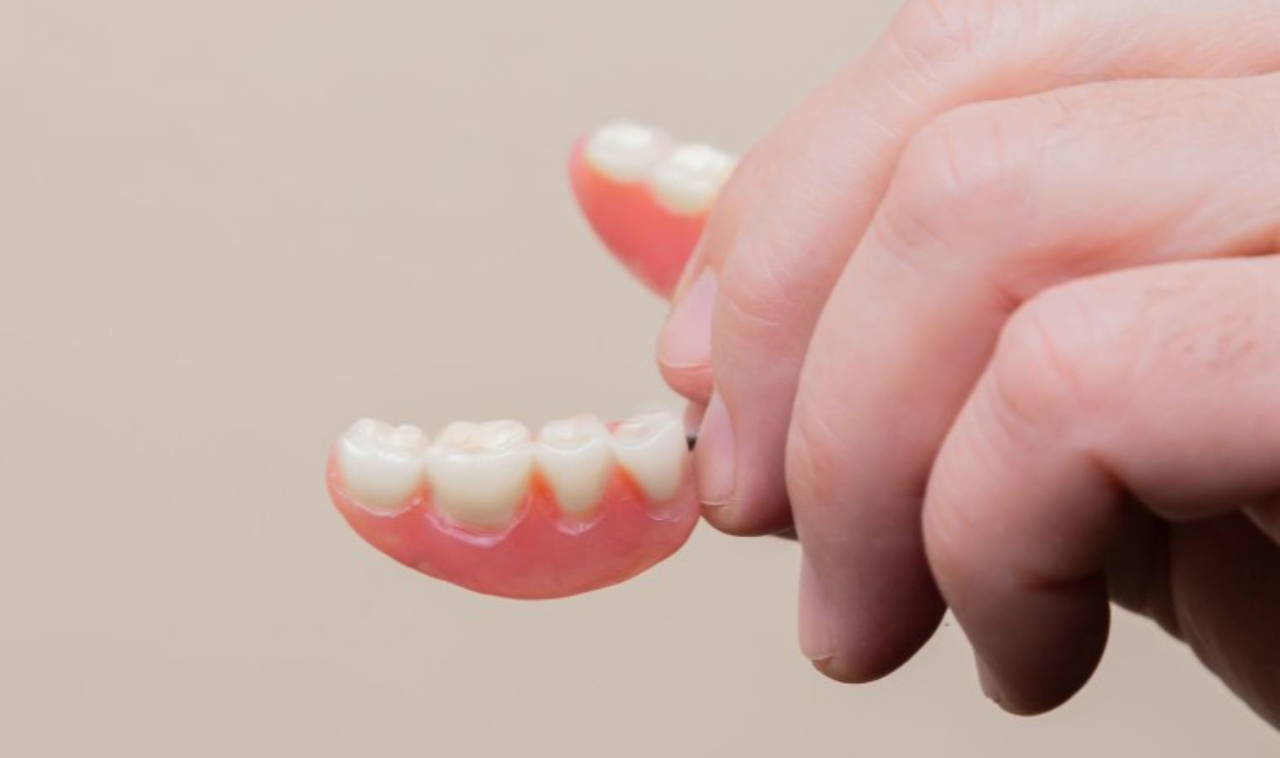

*Ateller ve ağız koruyucuları sıkma ve gıcırdatma nedeniyle oluşan hasarı önlemek üzere dişleri birbirinden ayrı tutmak için tasarlandı. Sert akrilik veya daha yumuşak malzemelerden yapılan bu araçlar üst veya alt dişlerin üzerine oturabiliyor.